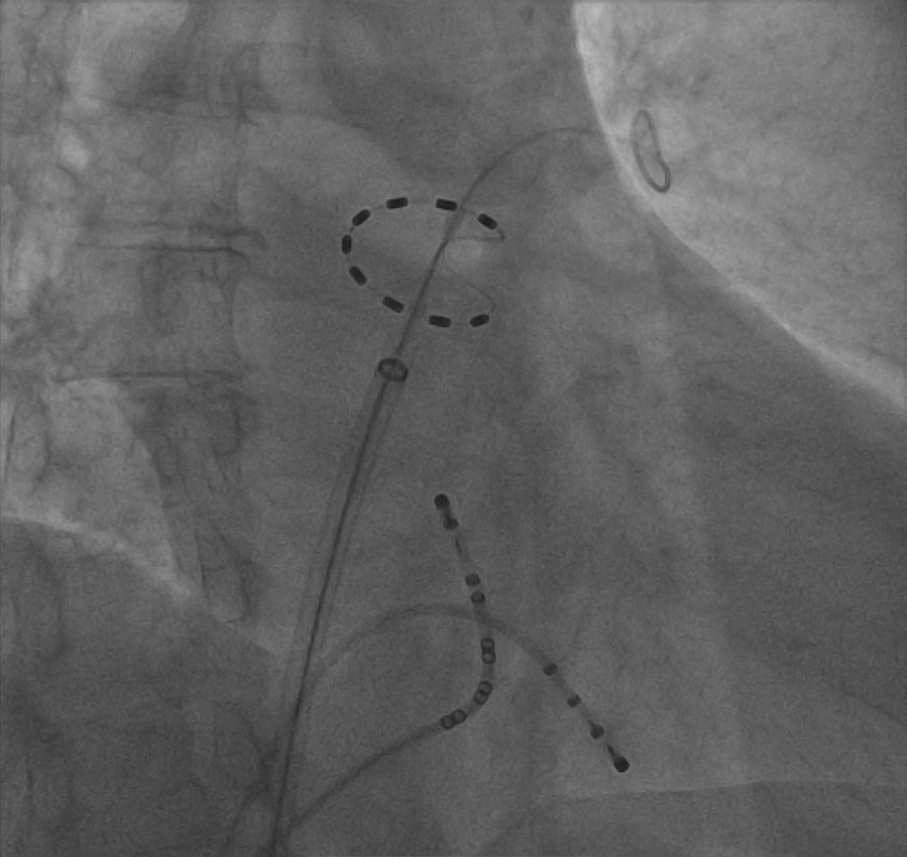

2025年2月13日首都医科大学附属北京潞河医院心律失常团队在翟光耀教授的指导下,在麻醉科全麻支持下,由高鹏副主任医师和陈文明主治医师为患者实施了PulseSelect™脉冲电场房颤消融术,左房操作时间仅30分钟。术后患者恢复良好,现已顺利出院后复查患者无主诉不适。

房颤以其高发病率、高致残率和高复发率的特点,被称为“隐形杀手”,目前我国房颤患者人数近2000万,房颤防治局面严峻。随着脉冲电场消融(PFA)的问世,房颤治疗进入了一个新的阶段。本次使用的PulseSelect脉冲消融导管,是25mm直径的中心导引的环形导管。9个黄金电极,全部都能实现标测、消融和起搏的功能,在现有三维标测系统下,导管均可完整显影;电极之间确保距离不变,保证电场稳定、消融效果连续可复制;同时,20°前倾设计,确保稳定贴靠。研究结果显示,仅0.7%不良安全事件发生率,奠定了安全性的基础。与传统能量相比,PulseSelect脉冲场消融技术的安全性更高,提高了治疗的有效性,是更安全高效的选择相信。潞河医院本次的新技术的开展,奠定了房颤消融领域的新的里程碑,医院与行业各大中心一起,为房颤患者提供更优质的诊疗技术。